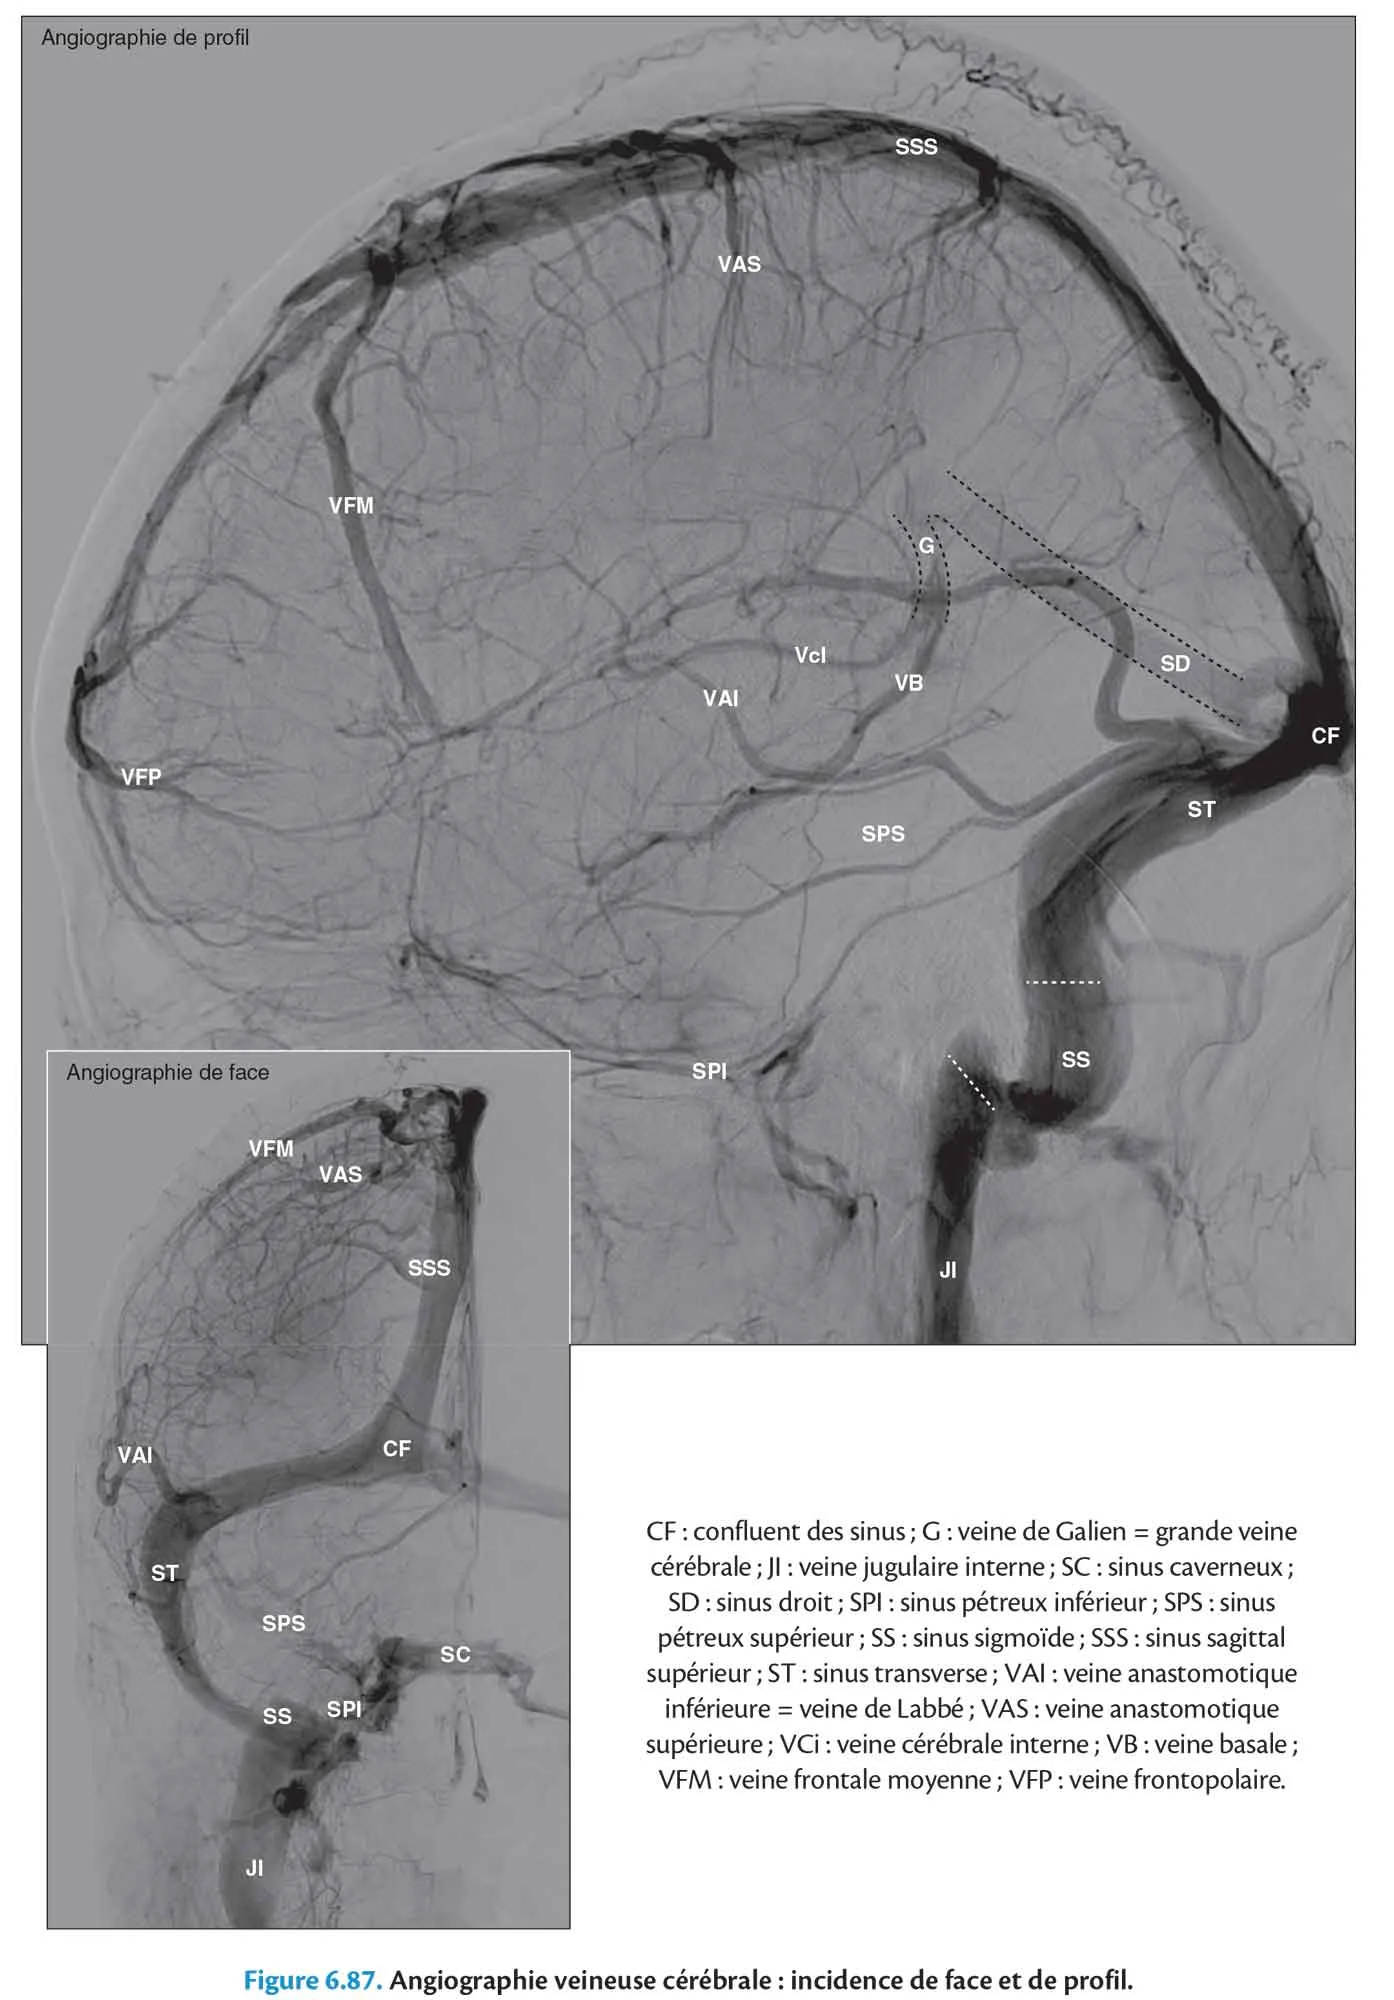

Angiographie de profil

Fig 6.87